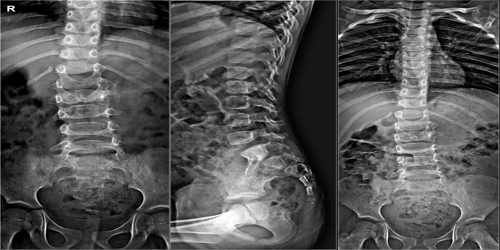

Рентген шейных позвонков при спина бифида

Раздел: Фотозарисовки